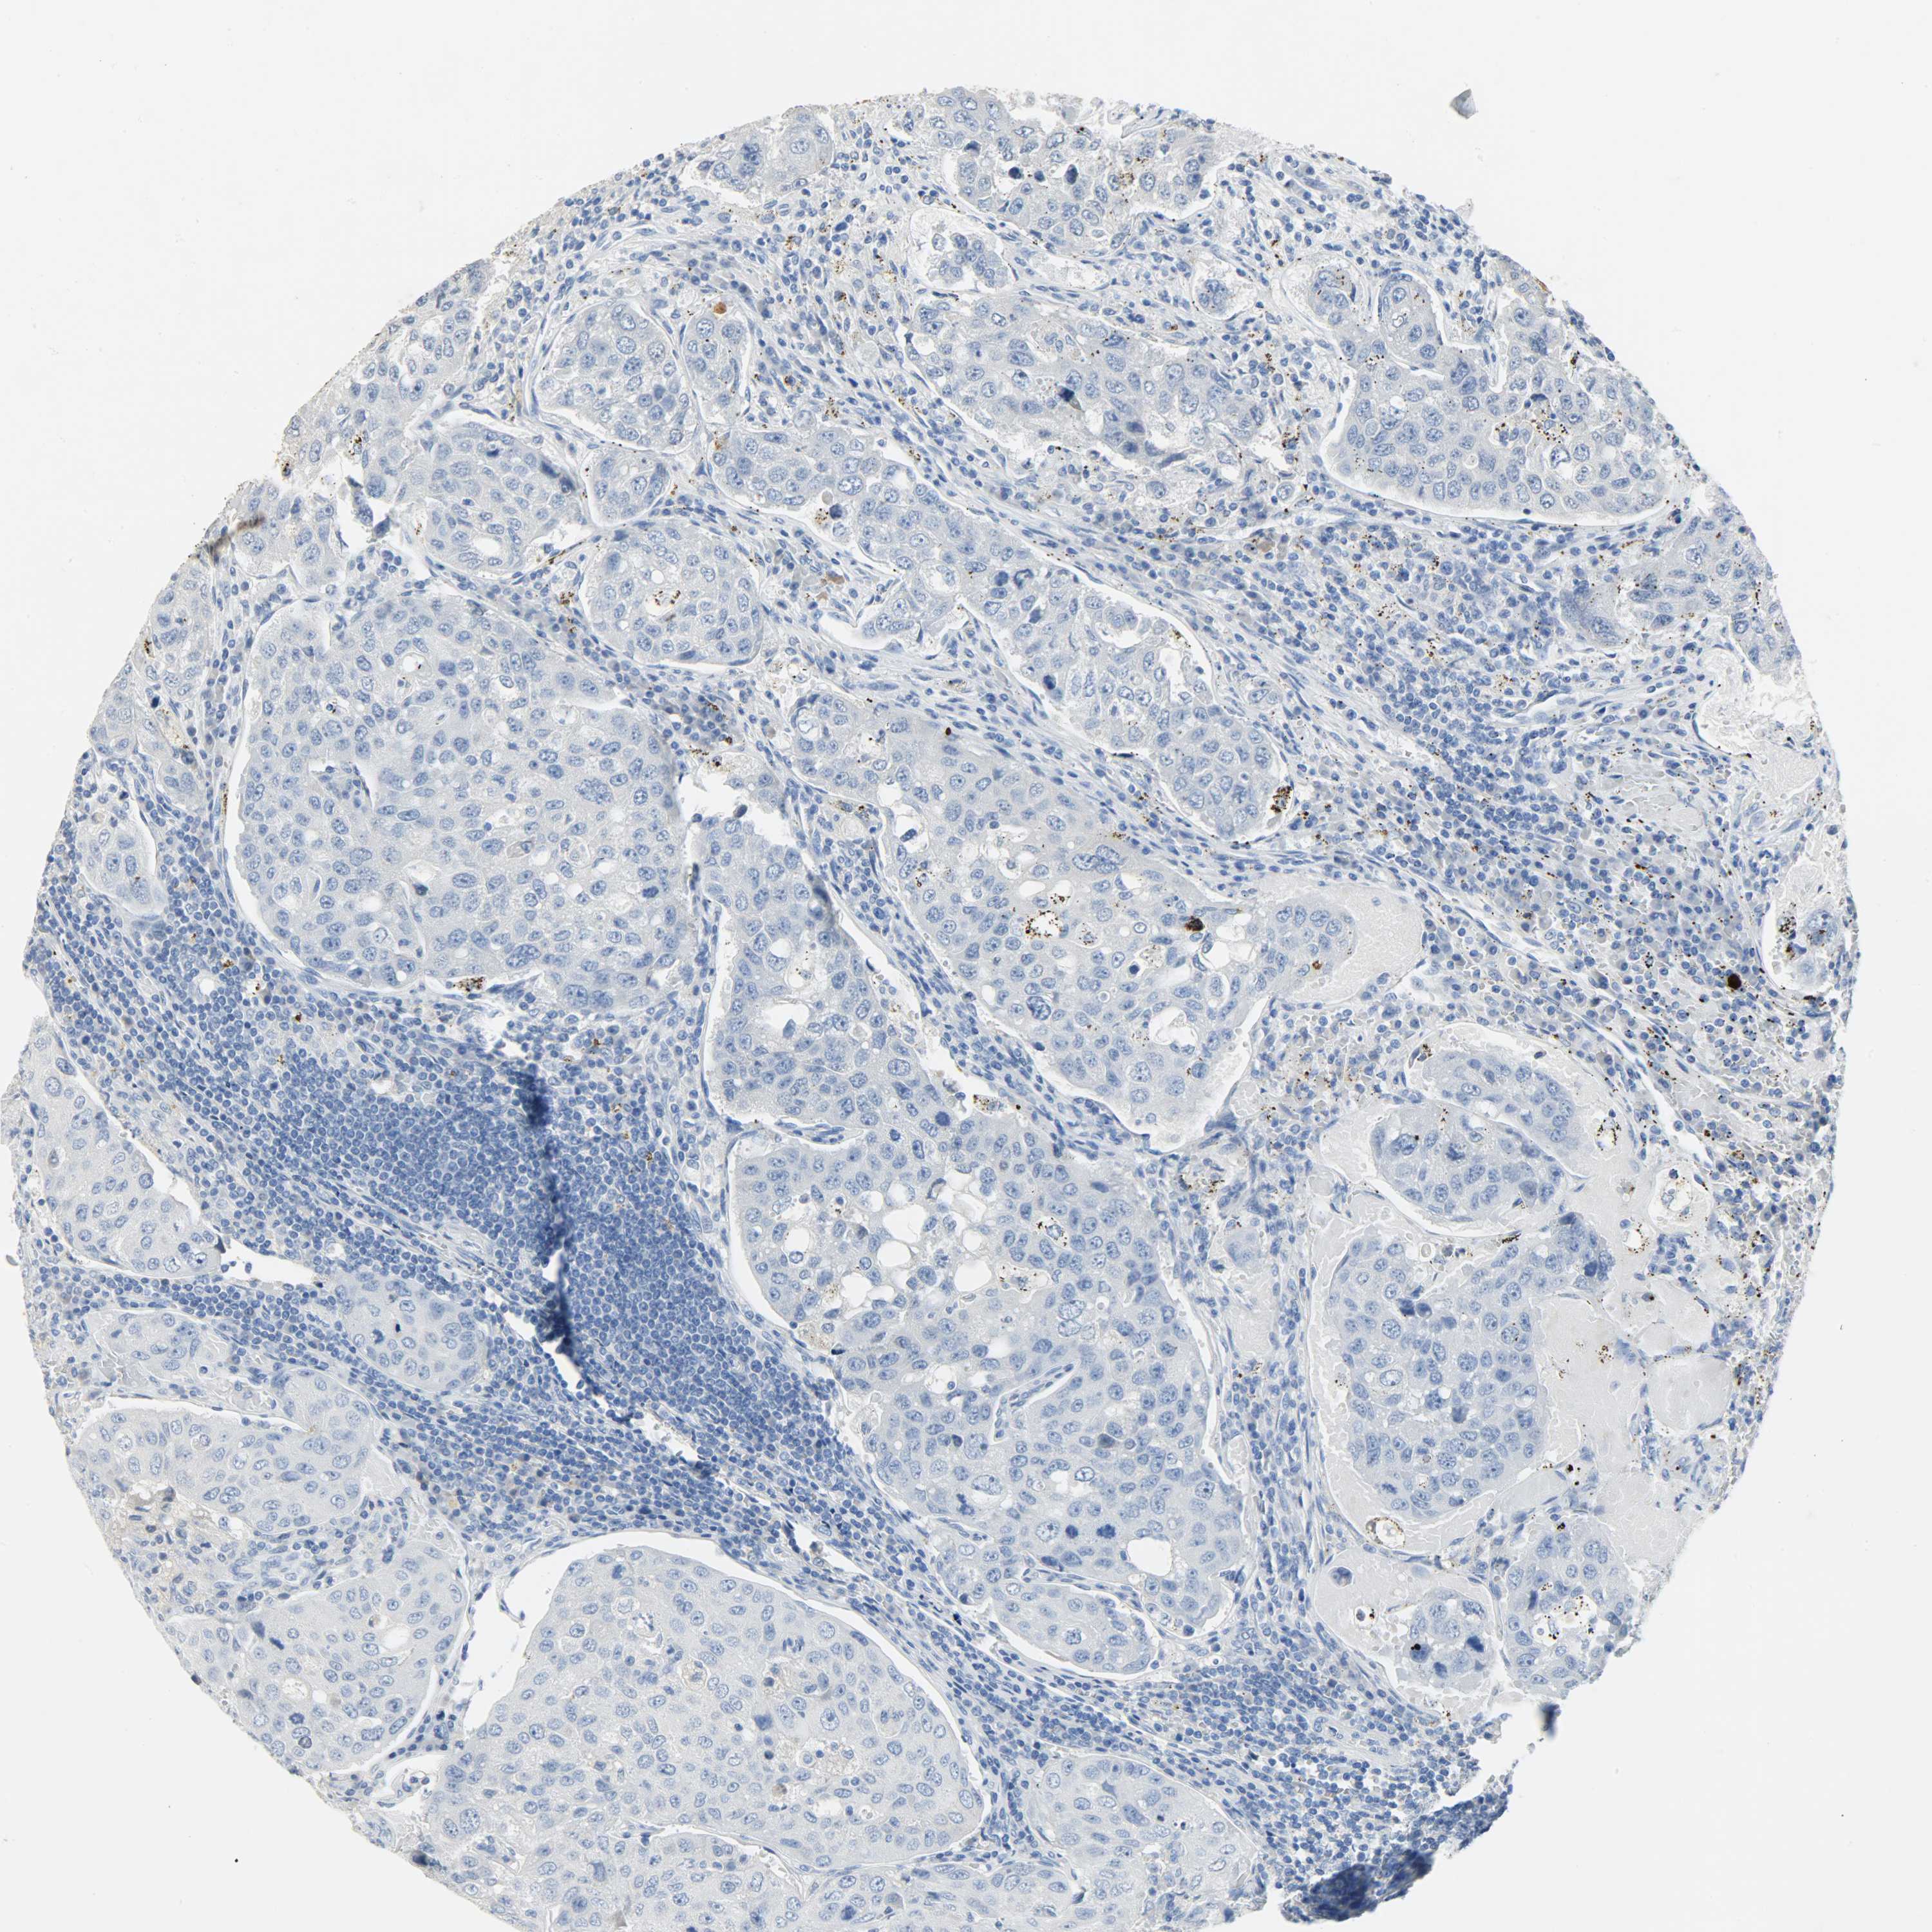

UROTHELIAL CANCER - Protein expressioni

A mouse-over function shows sample information and annotation data. Click on an image to view it in a full screen mode. Samples can be filtered based on level of antibody staining by selecting one or several of the following categories: high, medium, low and not detected. The assay and annotation is described here.

Note that samples used for immunohistochemistry by the Human Protein Atlas do not correspond to samples in the TCGA dataset.

Antibody stainingi

Antibody staining in the annotated cell types in the current human tissue is reported as not detected, low, medium, or high, based on conventional immunohistochemistry profiling in selected tissues. This score is based on the combination of the staining intensity and fraction of stained cells.

Each image is clickable and will lead to virtual microscopy that enables deeper exploration of all samples and also displays staining intensity scores, fraction scores and subcellular localization as well as patient and tissue information for each sample.

Antibody HPA027367

Antibody HPA027396

Antibody CAB005036

Staining

High

Medium

Low

Not detected

Intensity

Strong

Moderate

Weak

Negative

Quantity

>75%

75%-25%

<25%

None

Location

Nuclear

Cytoplasmic/membranous

Cytoplasmic/membranous,nuclear

Urothelial carcinoma, Low grade

Urothelial carcinoma, High grade